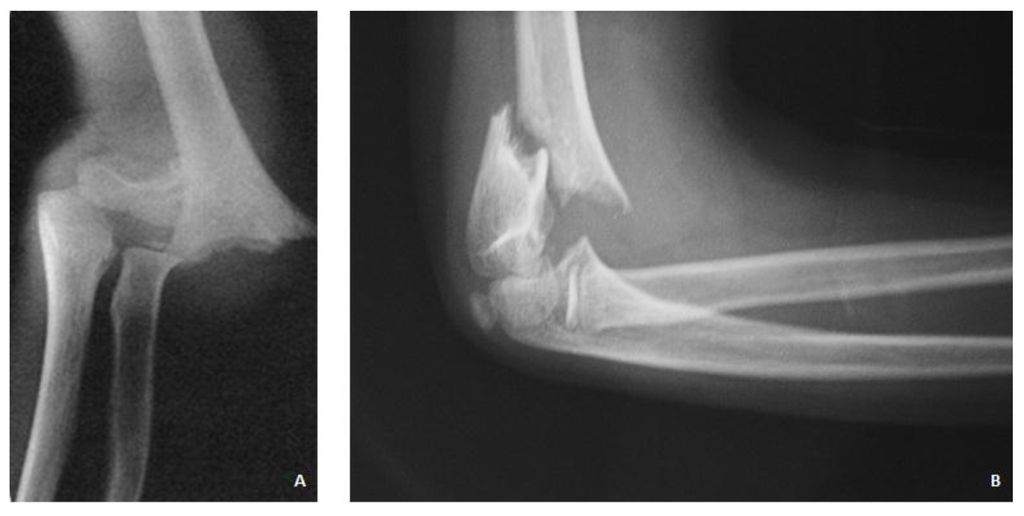

Surgical Treatment of Displaced Supracondylar Pediatric Humerus Fractures: Comparison of Two Pinning Techniques

:1. Introduction